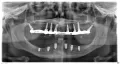

Хотелось бы узнать о стоимости и материале условно-съемного протеза на нижней челюсти, установлены 6 имплантат Нобель Биокаре.

• Как у Вас обстоят дела с первым слева имплантом? Дело в том, что на снимке вокруг него разрежение, вид такой, что с ним не все благополучно. Условно-съемный протез изготавливается из акриловой пластмассы или из термопластических пластмасс, с использованием пластмассовых импортных зубов. К сожалению, конкретно в наших клиниках протезирование на имплантаты, установленные не у н читать далее